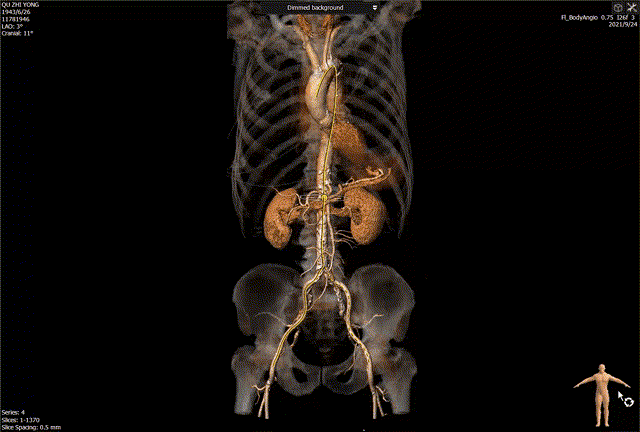

主动脉瓣CT评估:三叶瓣,双冠脉开口水平可,钙化分布较均匀。双侧髂股动脉内径可。瓣环长短径分别为17.9*25.1mm,周长为68.8mm,面积为358.1mm²。

血管入路评估: